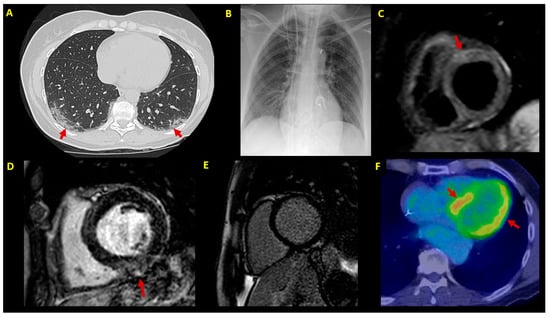

Figure 2.

Imaging findings. Imaging findings at patient (P1–P7) diagnostic workup. (A) Chest CT scan showing bilateral patchy ground-glass opacities (arrows) (P3); (B) chest X-ray in a patient (P7) with cardiogenic shock supported by IABP, VA-ECMO and temporary pacemaker; (C) CMR in a patient with infarct-like acute myocarditis associated with COVID-19 (P3); T2-STIR sequence shows edema in the anterior basal segment (arrow); (D) LGE sequences in a patient (P5) showing mild inferior mid-myocardial/subepicardial LGE (arrow); (E) absence of LGE by 3-month follow-up CMR in a patient (P4) with fulminant myocarditis at presentation; (F) 3-month follow-up FDG-PET scan in an ICD carrier (P5) with virus-negative myocarditis; abnormal left ventricular FDG uptake is shown (arrows). CMR = cardiac magnetic resonance; CT = computed tomography; EMB = endomyocardial biopsy; FDG-PET= 18F-fluorodeoxyglucose positron emission tomography; IABP = intra-aortic balloon pump; ICD = implantable cardioverter defibrillator; LGE = late gadolinium enhancement; LVEF = left ventricular ejection fraction; STIR = short-tau inversion recovery; VA-ECMO = venoarterial extracorporeal membrane oxygenator.